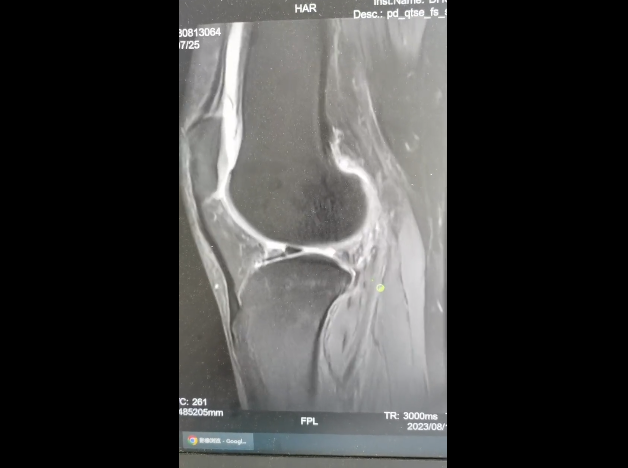

通过查体及辅助膝关节磁共振检查,明确诊断“右膝关节前交叉韧带断裂,外侧半月板撕裂”。